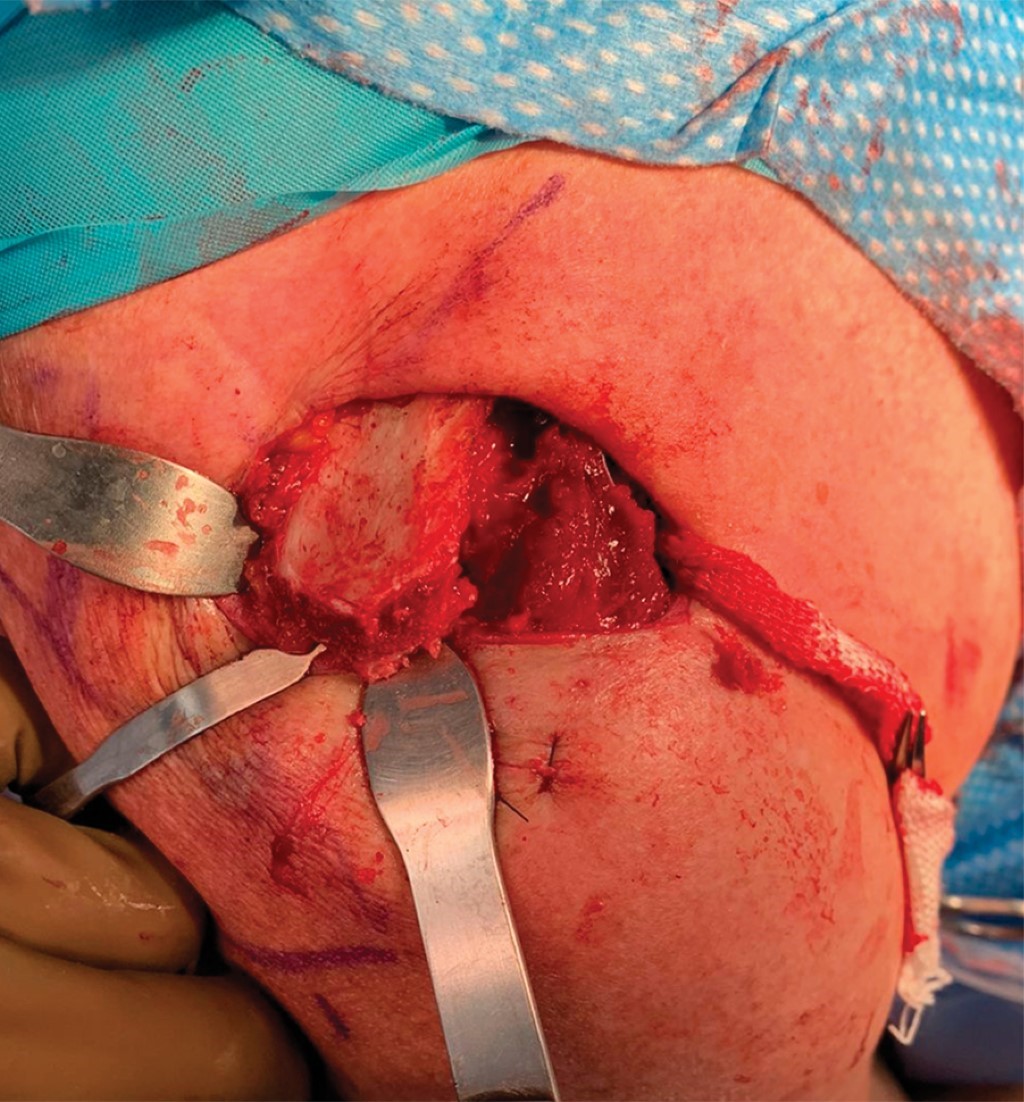

Se hace una incisión de 3 a 2 cm distal del borde lateral del acromion, por donde se pasa guía de nitinol por debajo del acromion. Se efectúa reducción manual de articulación AC, mientras un ayudante realiza fijación de injerto en los orificios de la clavícula con dos tornillos de biotenodesis 5 × 15 mm observando una adecuada fijación del injerto y restableciendo la estabilidad vertical (Figura 7). Posteriormente, el remanente de cabo distal del injerto se pasa por debajo del acromion con ayuda de la guía de nitinol en la incisión lateral y se sutura con su cabo proximal en el borde superior de la clavícula con una sutura no absorbible (Figuras 8 y 9).

El injerto además de servir para la reconstrucción de los ligamentos CC, su interposición en el espacio AC funciona como espaciador, reemplazando la función del disco articular de dicha articulación. Se toma un control fluoroscópico en proyección anteroposterior, corroborando adecuada reducción de articulación AC (Figura 10). Se procede a irrigar herida quirúrgica con Microdacyn. Se cierra cuidadosamente la fascia deltotrapezoidea con puntos interrumpidos con sutura absorbible (Vicryl 2.0) y posteriormente por planos: tejido celular subcutáneo con sutura Vicryl 2.0 con puntos invertidos en "U" y piel con sutura Stratafix 3-0 con puntos continuos subdérmicos. Se inmoviliza extremidad torácica con inmovilizador de hombro y banda aductora.

Figura 8

Figura 9